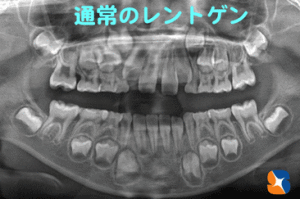

通常のレントゲンで歯並びを正しく予測するのは難しい

コラム「通常のレントゲンで歯並びを正しく予測するのは難しい」の画像